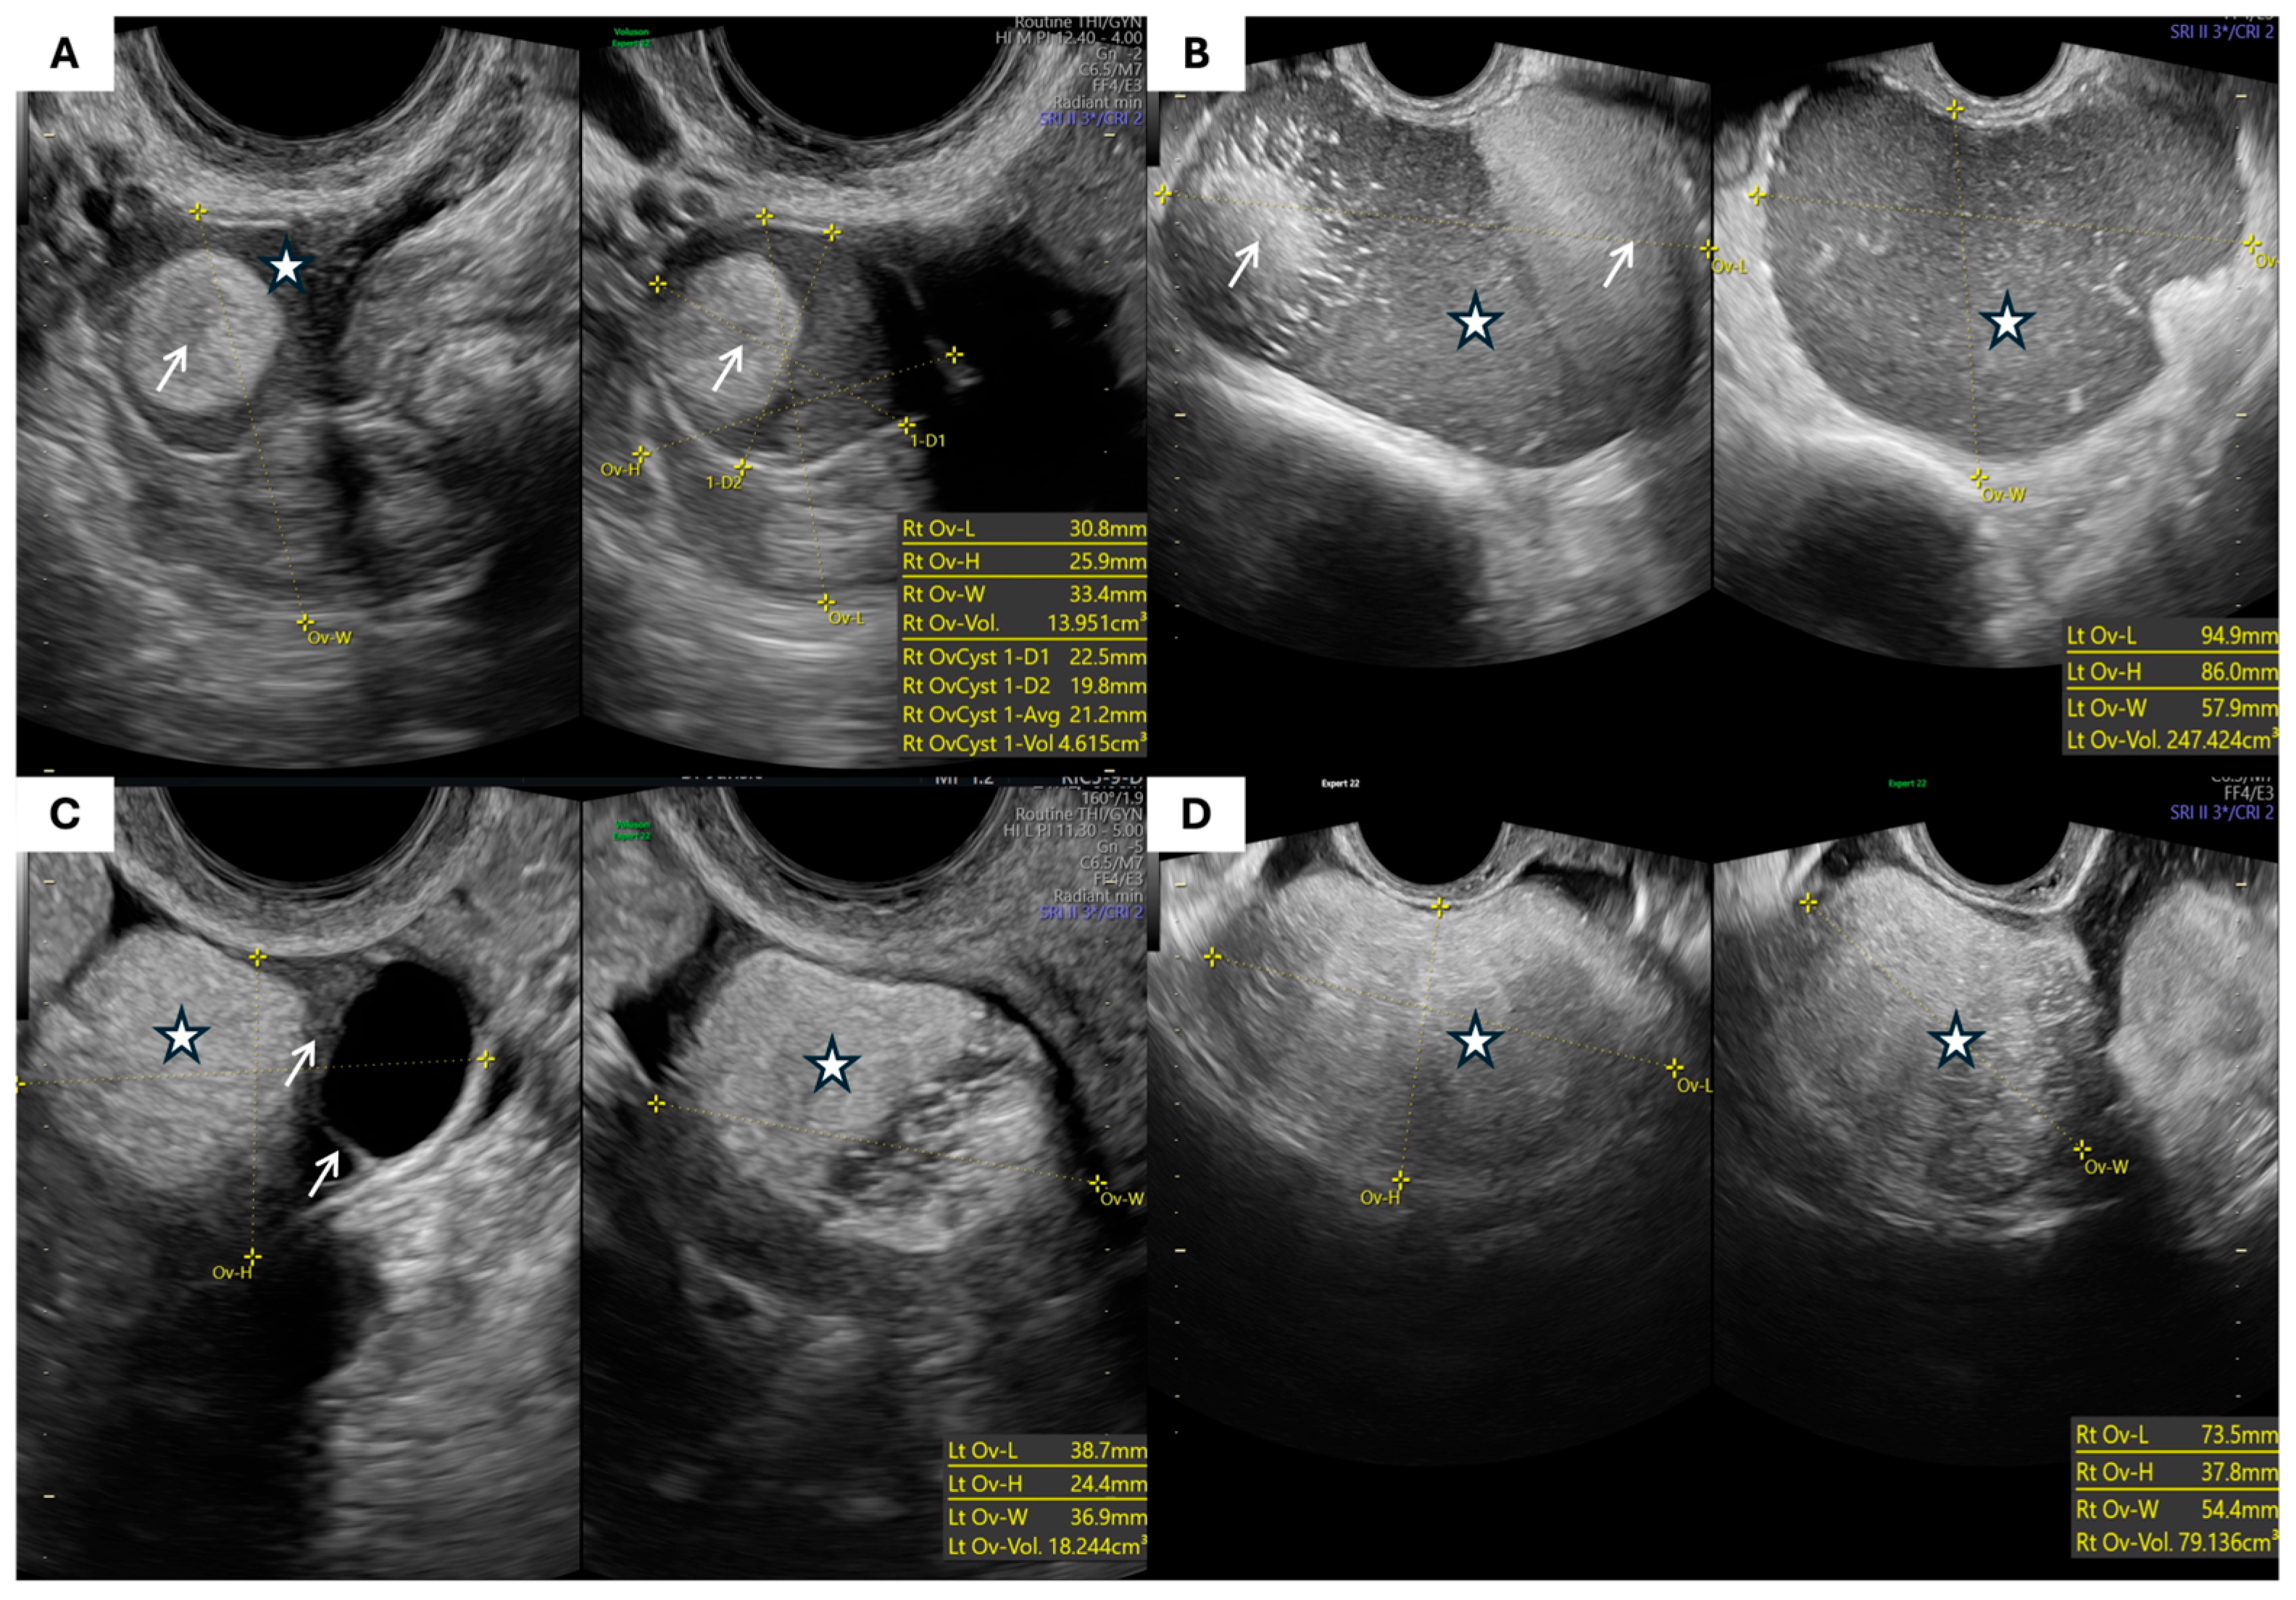

- Morphological Parameters: The morphological assessment included the largest tumor diameter, volume (calculated using the prolate ellipsoid formula: length × height × width × 0.523), laterality, capsule thickness, and internal echogenicity (categorized as anechoic, homogeneous low-level “ground-glass”, hyperechoic, or mixed/heterogeneous). The presence of septa, papillary projections, solid components, acoustic shadowing, free fluid in the pouch of Douglas, and signs of tumor fixation were also recorded.

| Morphological Type (IOTA Terminology) | Endometriomas (n = 55) | % | Teratomas (n = 49) | % | p-Value |

|---|---|---|---|---|---|

| Unilocular cyst with ground-glass echogenicity | 25 | 45.5% | 0 | 0% | <0.001 * |

| Unilocular solid cyst with hyperechoic content | 1 | 1.8% | 10 | 20.4% | |

| Multilocular cyst | 8 | 14.5% | 5 | 10.2% | |

| Multilocular solid cyst | 9 | 16.4% | 25 | 51.0% | |

| Cyst with papillary projections (unilocular or bilocular) | 1 | 1.8% | 1 | 2.0% | |

| Solid tumor | 3 | 5.5% | 4 | 8.2% | |

| Other/not otherwise specified | 8 | 14.5% | 4 | 8.2% |